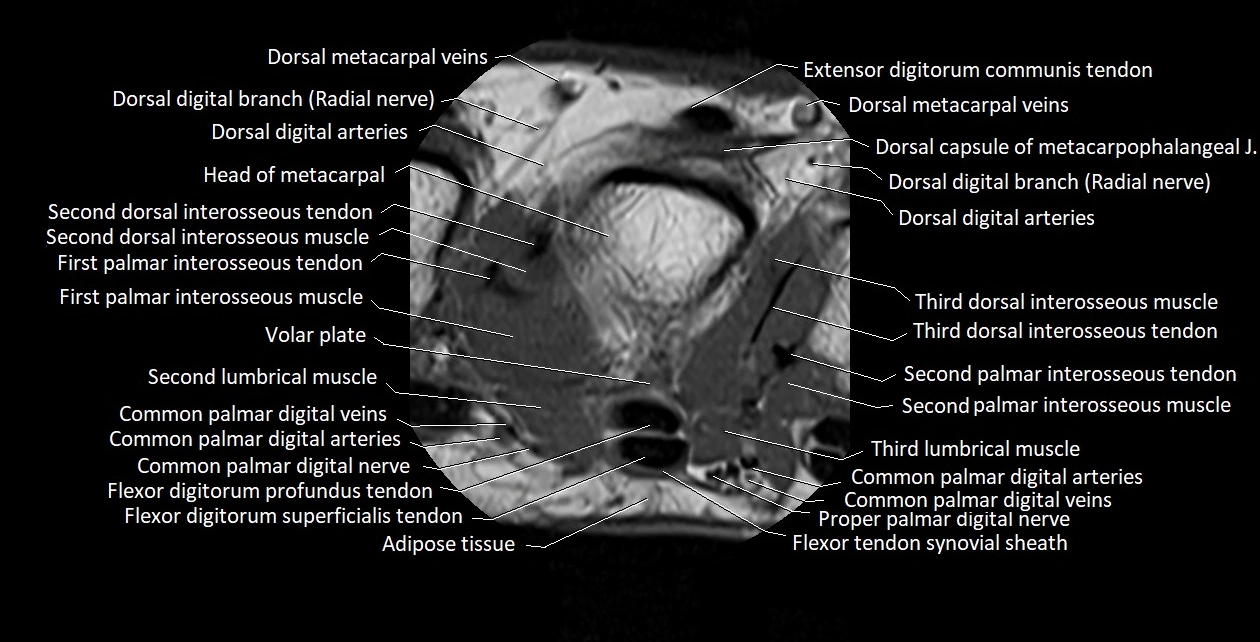

MRI images